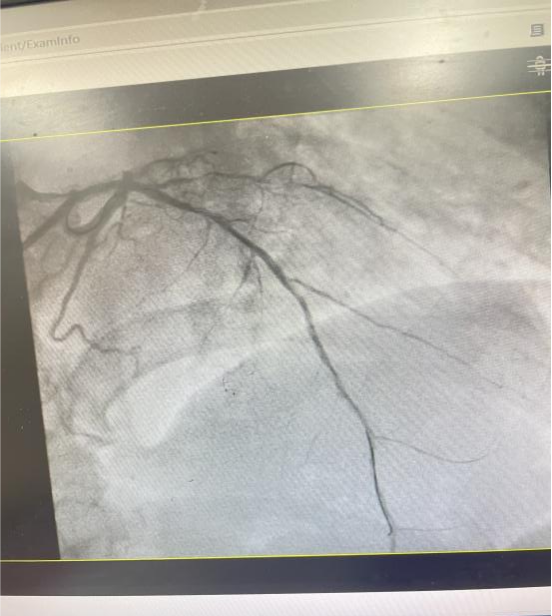

60岁的何叔叔因反复胸闷4天入院。入院后行冠脉造影示: 左主干开口狭窄约80%,前降支中段见局限性狭窄约90%;中间支近段慢性闭塞,PD、PL均有较重病变,狭窄70%-85%不等,前向血流TIMI 3级。考虑血管病变重,手术风险高、难度很大,与何叔叔及家属沟通后建议择期行IVUS检查+PCI术。

前降支中段血管闭塞

前降支中段血管开通